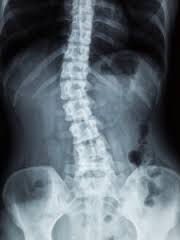

Low back pain refers to pain that you feel in your lower back. You may also have back stiffness, decreased movement of the lower back, and difficulty standing straight. Low back pain that is long-term is called chronic low back pain.

Many people with chronic back pain have arthritis. Or they may have extra wear and tear of the spine, which may be due to:

You may have had a herniated disk, in which part of the spinal disk pushed onto nearby nerves. Normally, the disks provide space and cushion in your spine. If these disks dry out and become thinner and more brittle, you can lose movement in the spine over time.